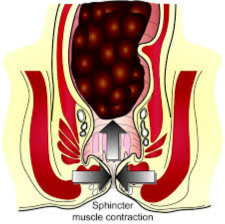

Sphincter Repair for Incontinence

This procedure repairs a damaged or weakened anal sphincter that occurred during childbirth. Doctors identify an injured area of muscle and free its edges from the surrounding tissue. They then bring the muscle edges back together and sew them in an overl